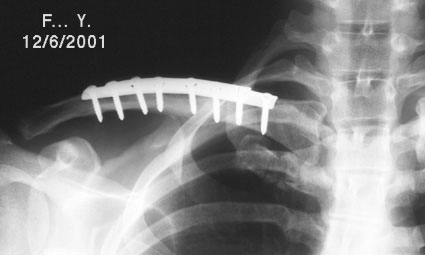

Image n° 1: Pre-operative X-rays

|

|

Image n° 2: Bone healing

|

|